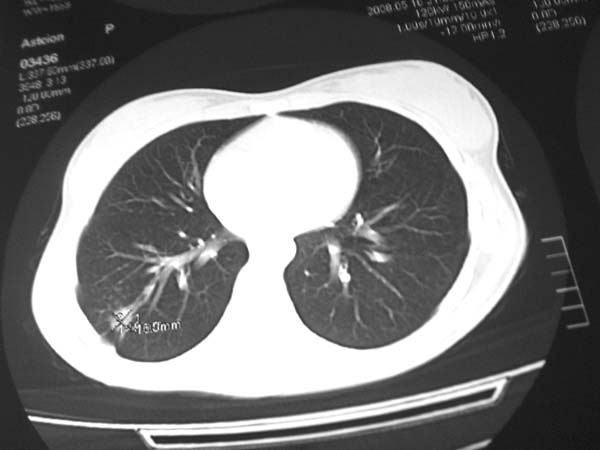

标题: CT13486:F 17Y 咳嗽 咳痰数日请会诊 [打印本页]

标题: CT13486:F 17Y 咳嗽 咳痰数日请会诊

白细胞9600不发烧

考虑右下结核球

右肺下叶结核灶

右下肺背段病灶,考虑结核与炎症鉴别,请进一步检查.

考虑为:右肺下叶外基底段结核球。

结果;痰中找到结核杆菌

痰涂片已找到结核杆菌  将结果告诉大家